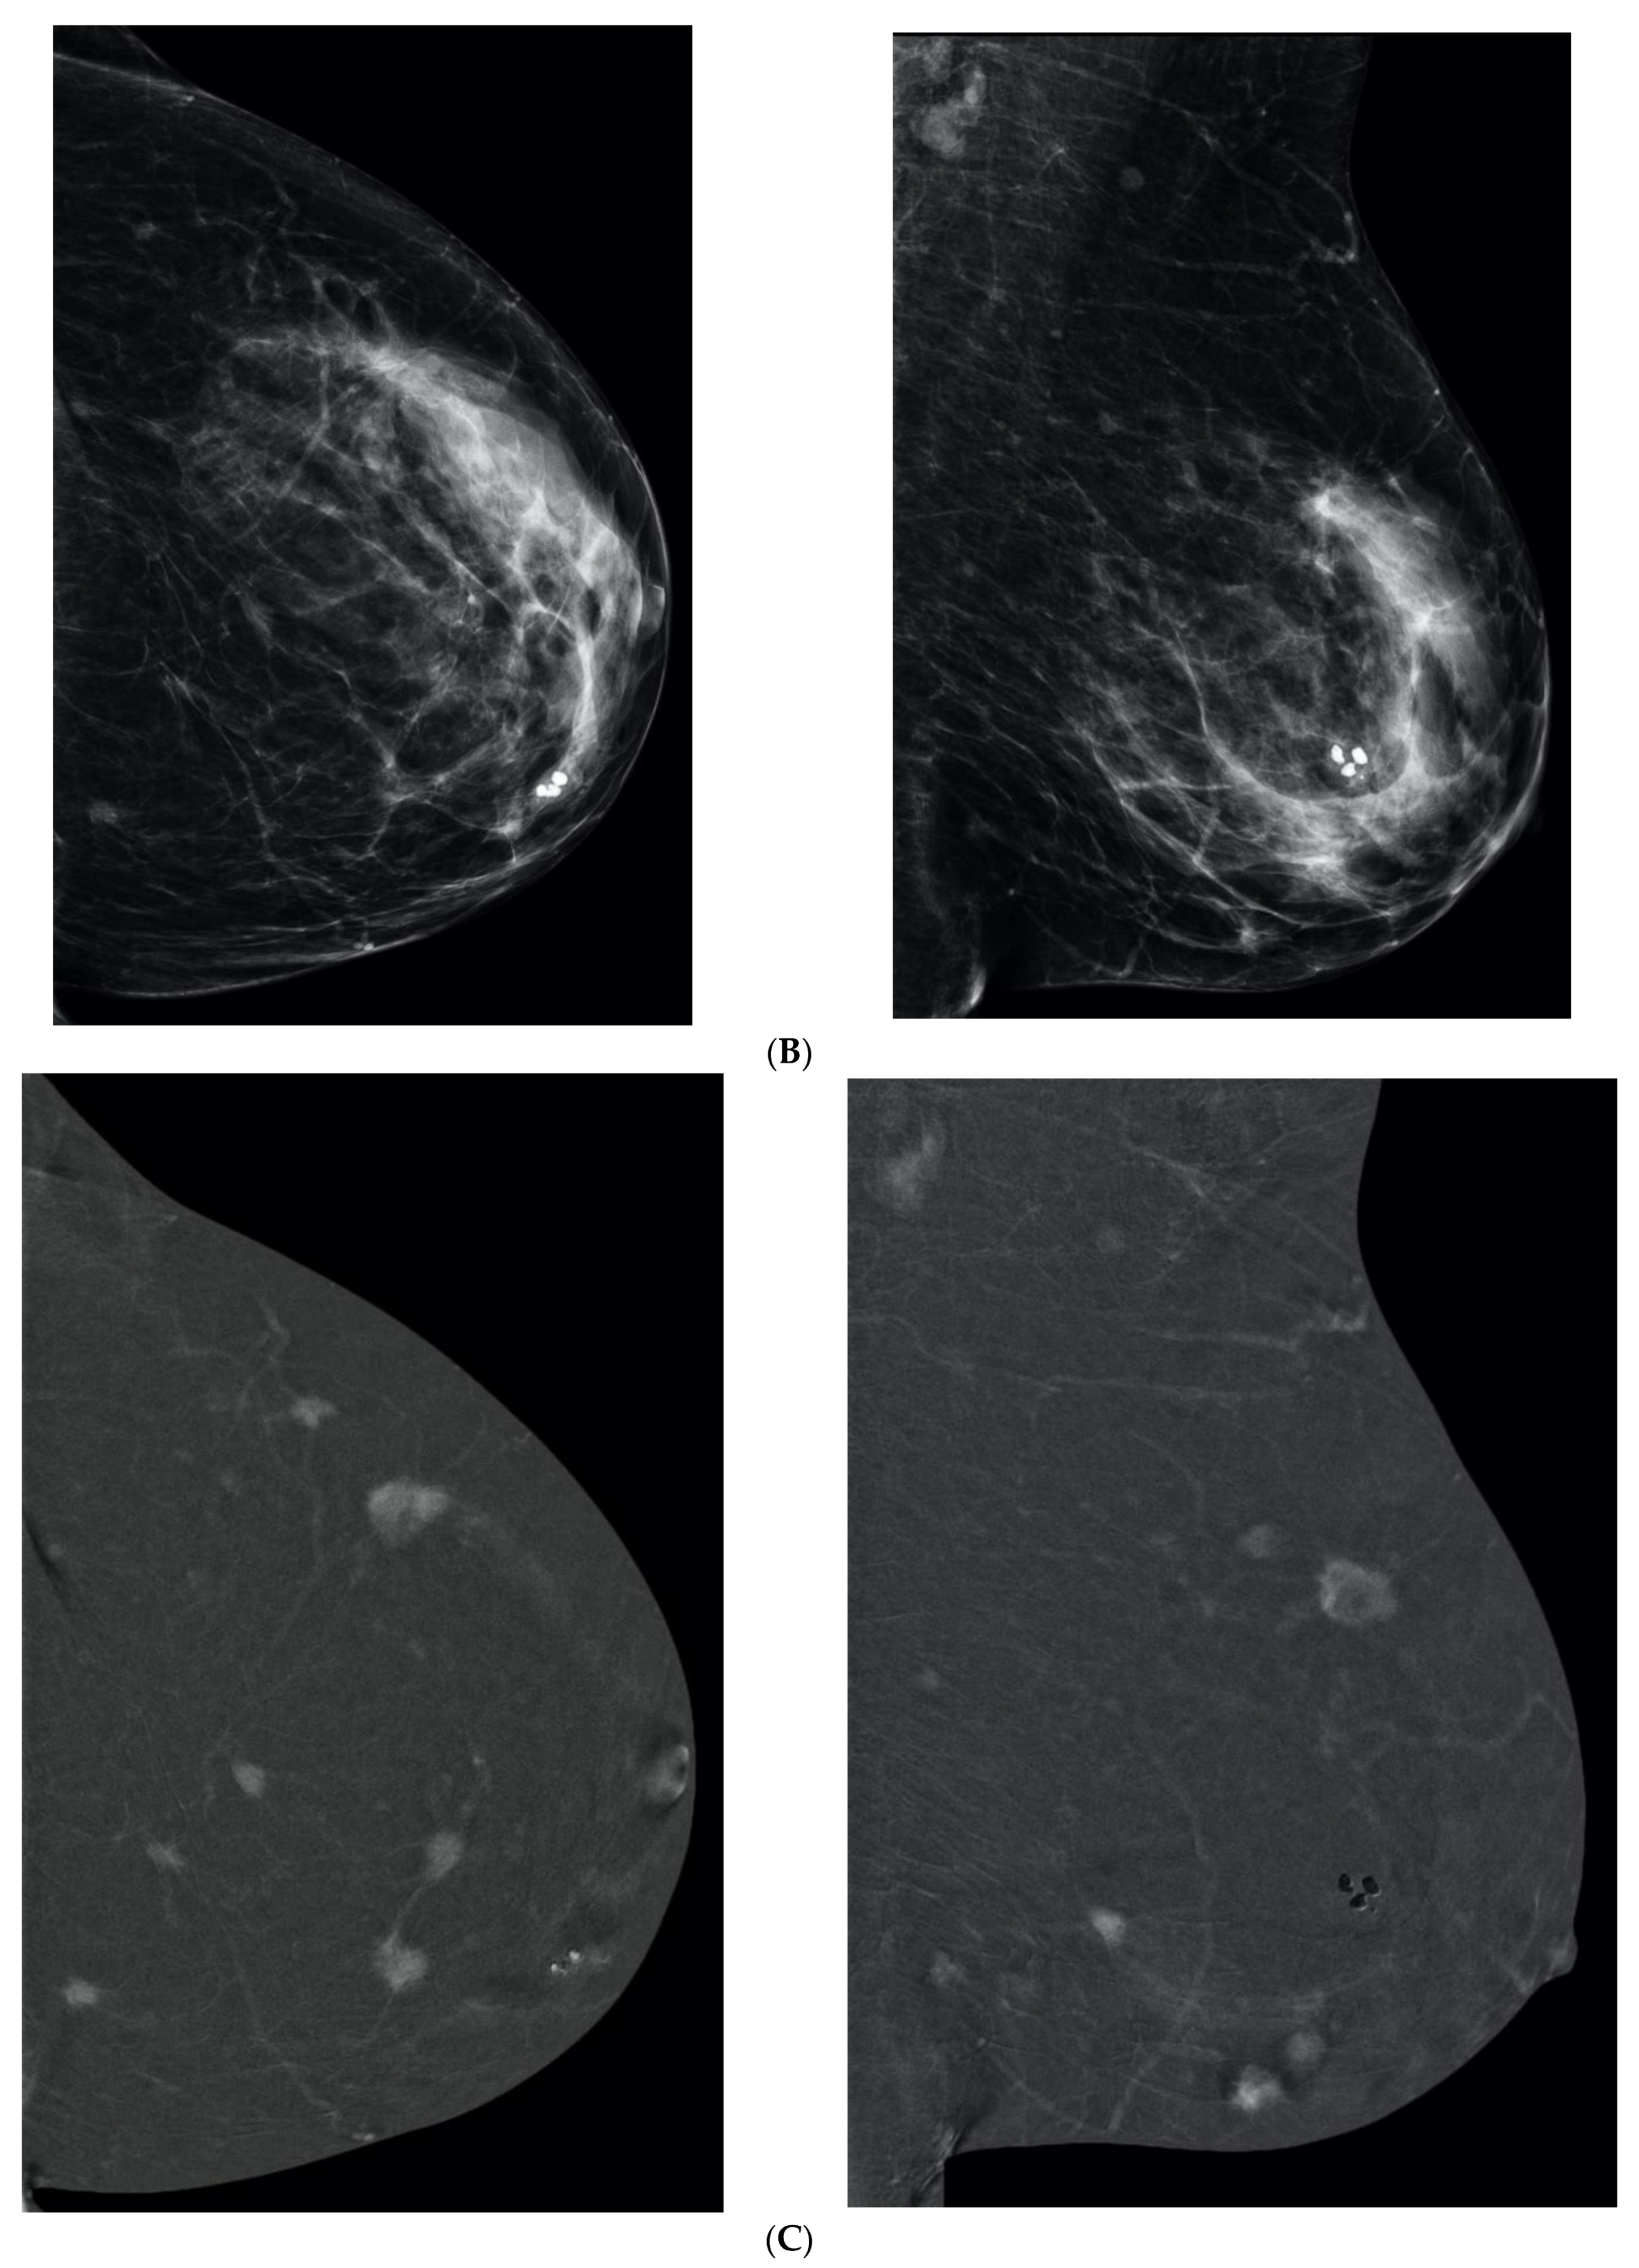

6. Digital Breast Tomosynthesis (DBT)

7. Magnetic Resonance Imaging (MRI)

8. Contrast-Enhanced Mammography (CEM)